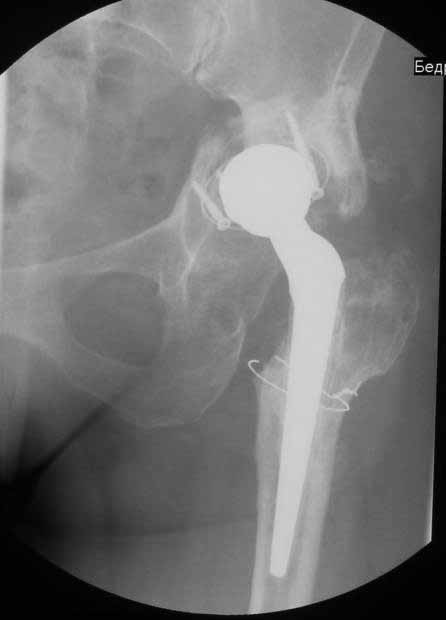

Уважаемые коллеги. Хотелось бы услышать мнения и советы по представляемому случаю.

Пациентка 45 лет. Бесцементное эндопротезирование левого тазобедренного сустава 6 лет

назад (впадина RM, Mathys, металл-металл, ножка Зульцеровская). За 10 лет до

протезирования коррегирующая остеотомия бедренной кости, которая не срослась в течение

года до удаления пластины, а затем срослась в течение 3 месяцев иммобилизации в кокситной

повязке. После протезирования получилось наблюдать пациентку почти постоянно, поскольку

через 2 года синтезировал ей лодыжки на оперированной стороне, затем, через несколько

месяцев удалил фиксаторы, а в 2009г. резецировал мениск на противоположной стороне. Боли

все эти годы не беспокоили. Пациентка чуть выше среднего роста, вес тела нормальный.

Физические нагрузки переносила хорошо. Работает на 7 этаже без лифта. Год назад экстирпация

матки по поводу лейомиомы больших размеров. Несколько месяцев назад появились боли в

области левого тазобедренного сустава. При рентгеновском и КТ исследованиях (июль с.г.)

нестабильность тазового компонента. От предложенной замены протеза пациентка на тот

-Если думать о ревизии, то когда? На представленных снимках тазобедренный сустав до и

сразу после операции, затем 2 снимка 2009г., когда ничего не беспокоило, затем КТ 2-х

месячной давности и вчерашние рентгенограммы обоих тазобедренных суставов.